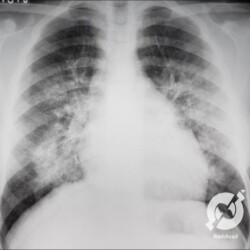

Aumento do volume cardíaco, inversão da circulação pulmonar, lesões intersticiais reticulares com linhas B de Kerley bilaterais e obliteração do seio costofrênico direito.